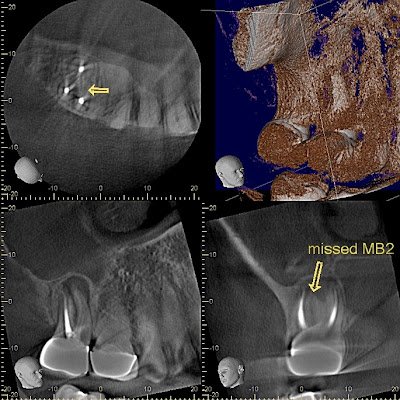

This root canal was treated by another endodontist and then retreated after symptoms failed to resolve. She came to Superstition Springs Endodontics for a second opinion. The obturated roots look filled to an ideal length.

CBCT reveals a missed MB#2 canal. Blue outline shows an axial slice of the MB root. The pear-shaped root outline reveals the missed canal.

The sagittal view also shows the MB#1 canal is off center of the long axis of the root. A lesion into the sinus cavity is noted. Note the distinct MB lesion visible in the CBCT. I explained to the patient that it would be the other endodontist would likely retreat this tooth at no charge, but this patient has elected to retreat the tooth in our office.

The CBCT is a map for retreatment. It tells us exactly where to look to find the missing canal.